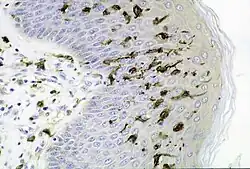

O corpo humano consiste em muitas categorias de tecidos, definidos como células que atuam com uma função especializada.[56] O estudo dos tecidos é denominado histologia e geralmente ocorre com um microscópio. O corpo consiste em quatro tipos principais de tecidos; células de revestimento (epitélios), tecido conjuntivo, tecido nervoso e tecido muscular.[57]

As células que se encontram em superfícies expostas ao mundo exterior ou trato gastrointestinal (epitélio) ou cavidades internas (endotélio) vêm em várias formas e formas; de camadas únicas de células planas a células com pequenos cílios como nos pulmões, para células como colunas que revestem o estômago. As células endoteliais são células que revestem as cavidades internas, incluindo vasos sanguíneos e glândulas. As células de revestimento regulam o que pode ou não passar por elas, protegem as estruturas internas e funcionam como superfícies sensoriais.[57]